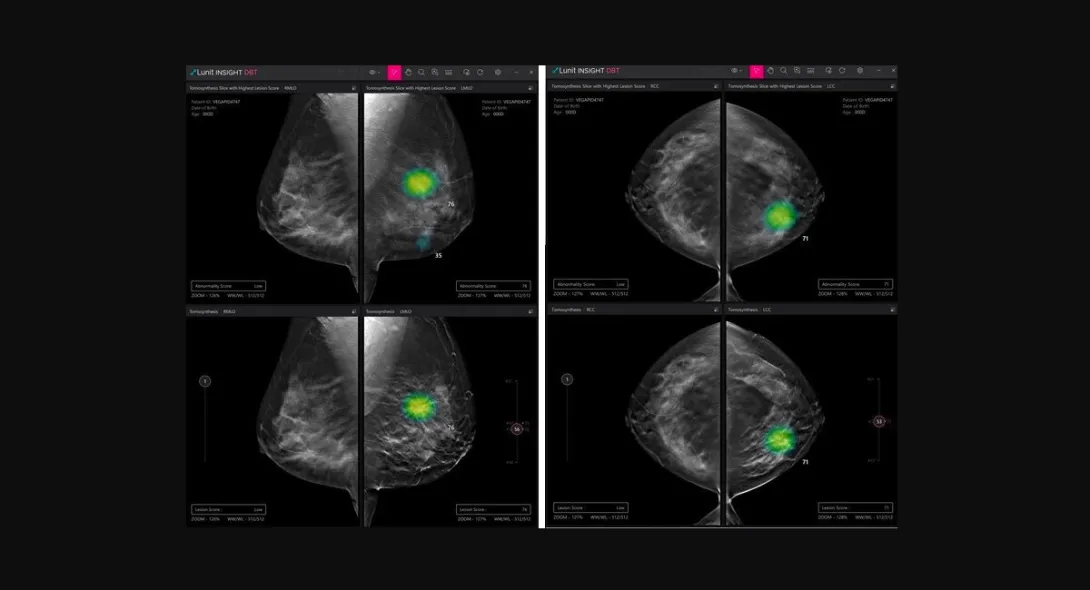

South Korean medical AI company Lunit has received a CE mark under Europe's latest Medical Device Regulation for its AI software for digital breast tomosynthesis (DBT) analysis.

Called Lunit INSIGHT DBT, the software solution analyses 3D images from DBT, enabling fast and accurate diagnosis of breast cancer.